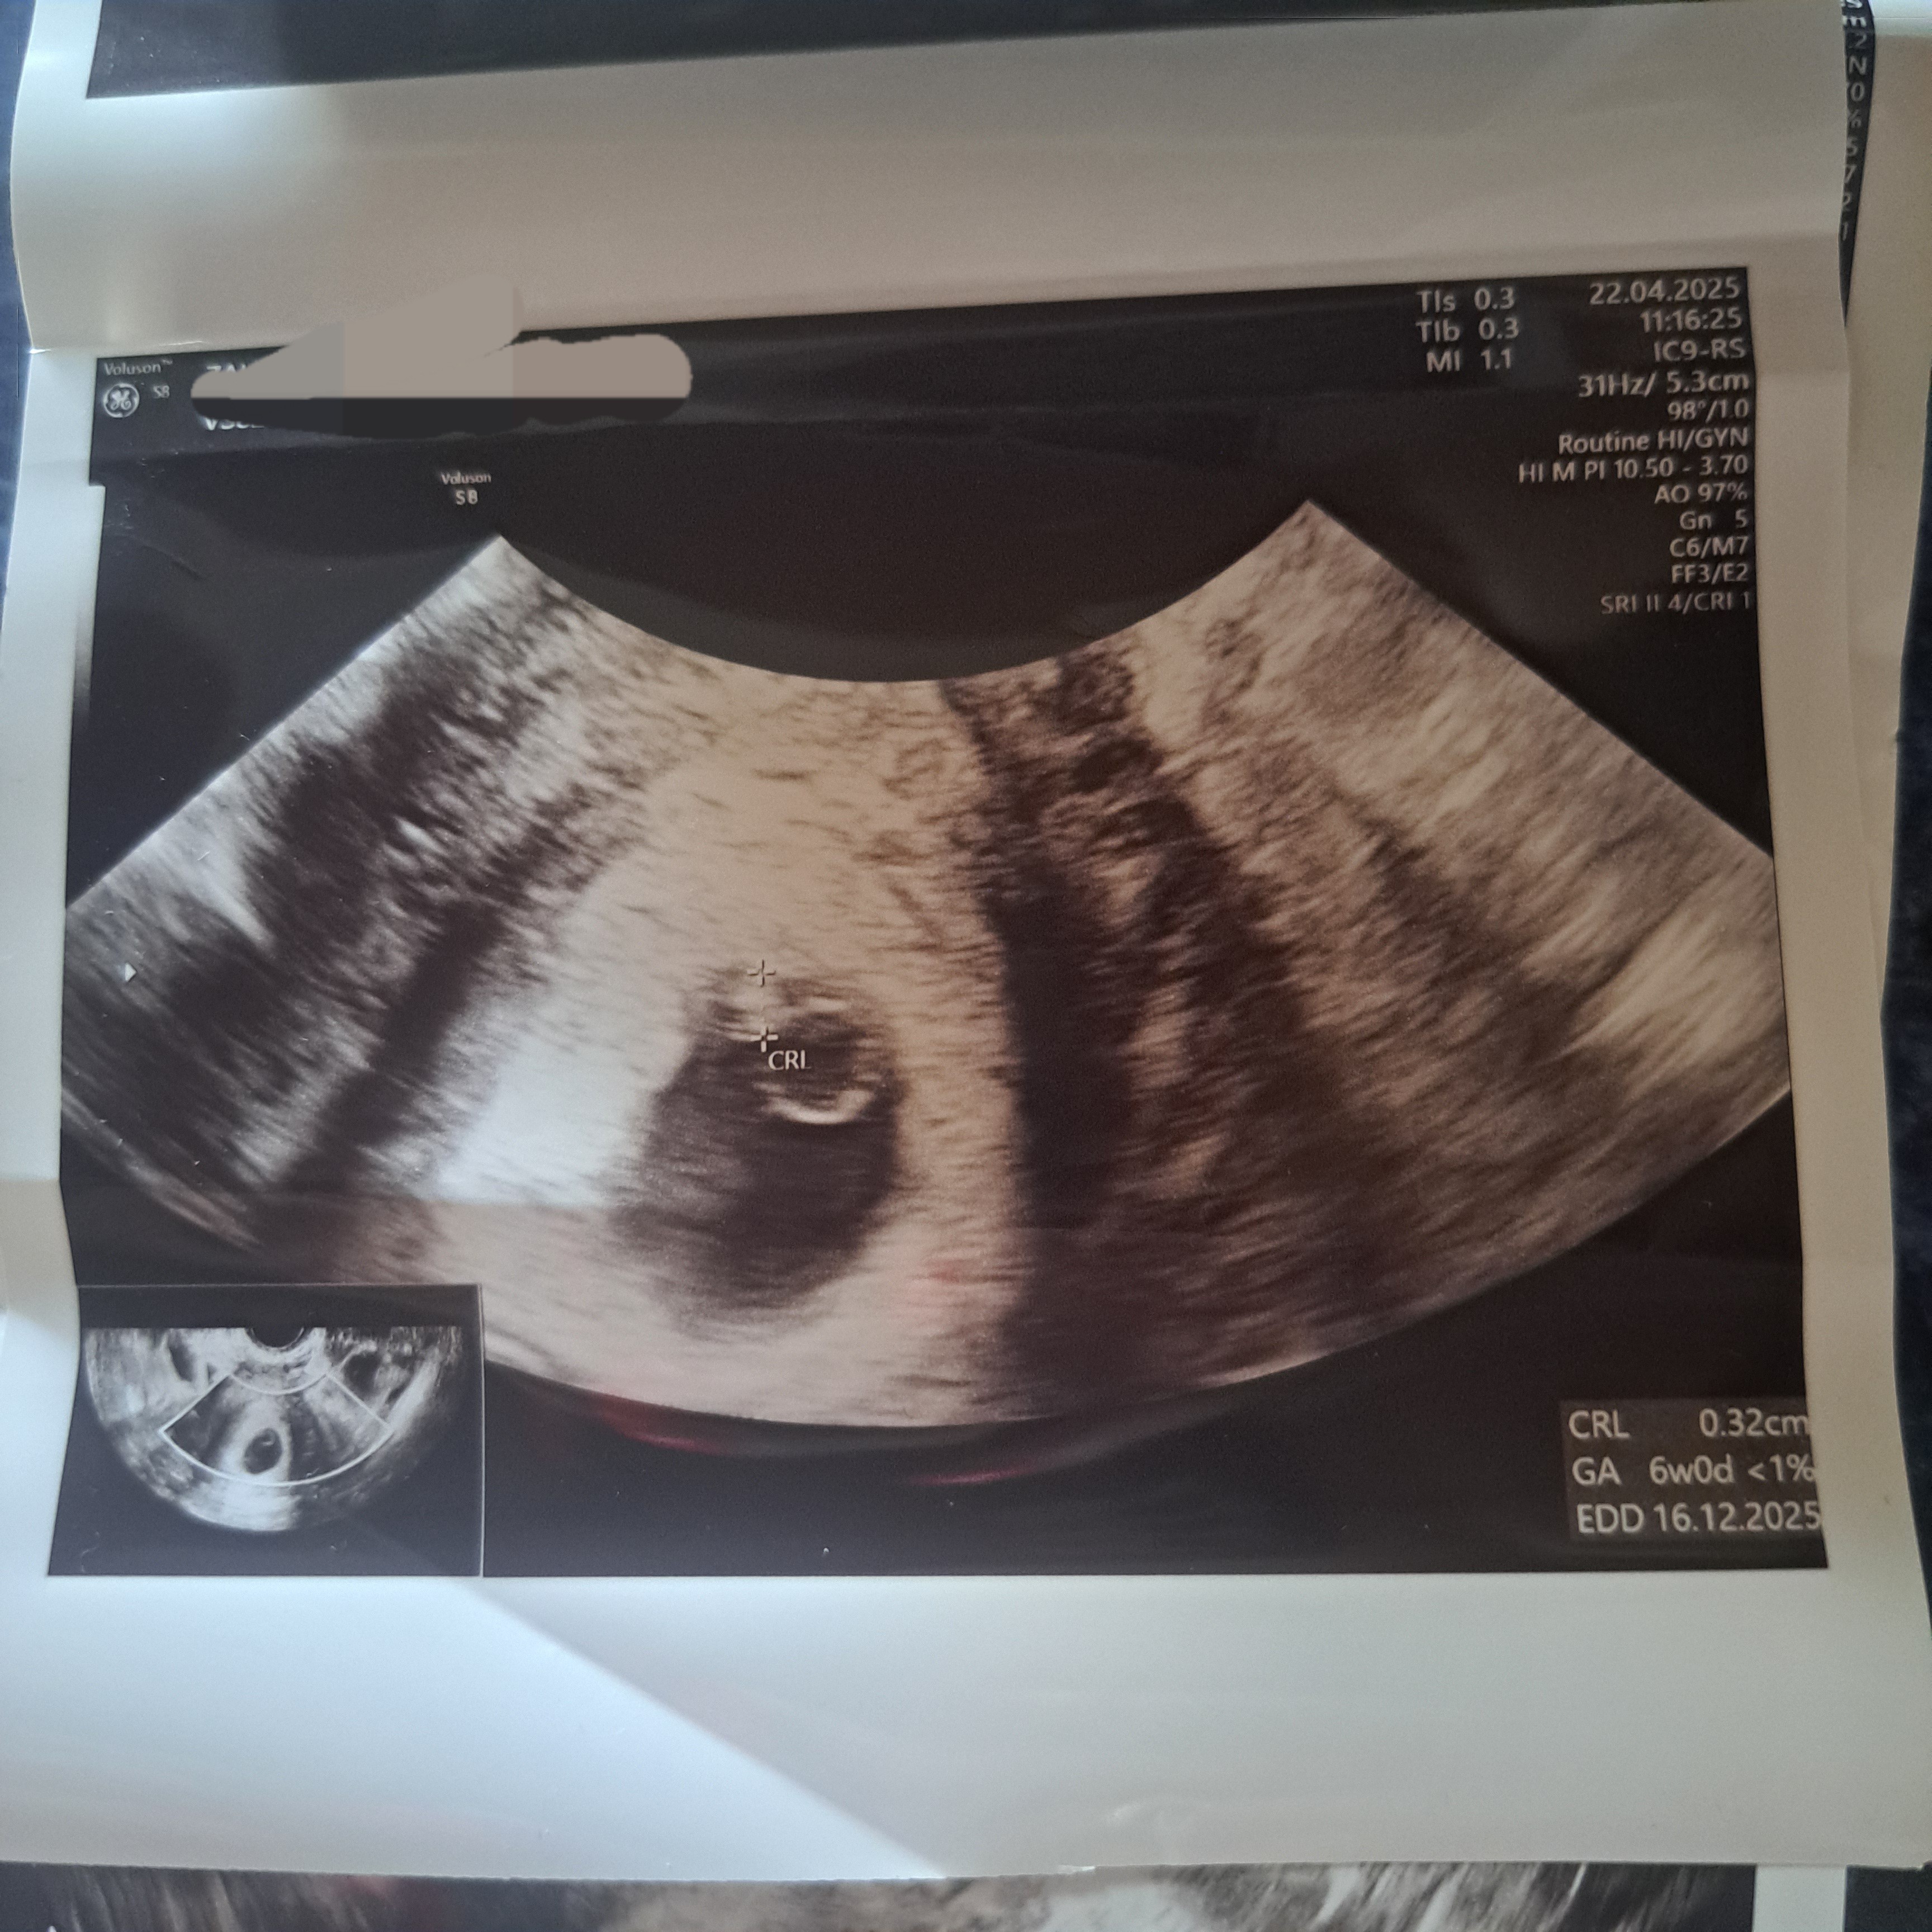

Pierwsze z wczoraj drugie sprzed 2 tyg.

Jest pęcherzyk ciążowy, żółtkowy i zarodek. Co prawda masz tam, że zarodek jest na 6+0 a Ty byłaś z tego co pisałaś w wyższej ciąży. I zarodek nie wykazał co prawda akcji serca. Ale trzeba pamiętać, że to są minimetry. Wystarczy lekkie ruszenie inne zaznaczenie i już będzie się wszystko zgadzać.